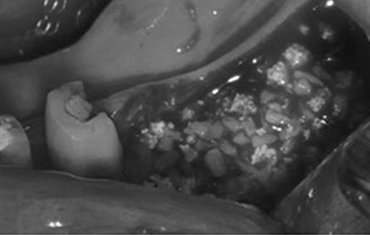

뼈의 길이는 좋으나 폭이 부족

임플란트 식립과 동시에 뼈이식을 하는 경우

폭이 많이 부족하여 뼈이식을 먼저 한 후, 임플란트 식립을 하는 경우